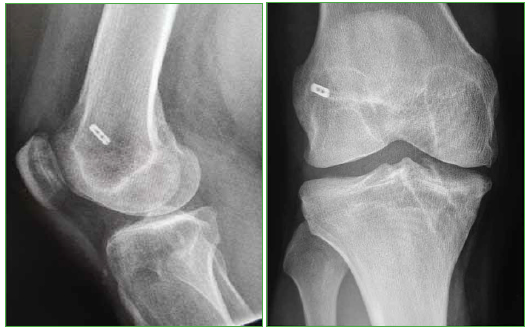

Se trata de dos series de 30 pacientes operados por el mismo cirujano utilizando injerto autólogo múltiple, de tres a cinco fascículos, de tendones autólogos homolaterales semitendinoso y recto interno, y empleando, en una de ellas, la técnica monotúnel transtibial con guía over the top para la tunelización femoral y, en la otra, la técnica bitúnel con tunelización retrógrada ciega femoral mediante FlipCutter® (Arthrex, Naples, FL, EE.UU.), fijando la plastia, en ambas técnicas, con el sistema cortical ACL TightRope® (Arthrex, Naples, FL, EE.UU.) a nivel proximal y con tornillo retrógrado interferencial (Arthrex, Naples, FL, EE.UU.) a nivel distal. La inserción tibial de la plastia se ubicó en la zona posterior de la huella anatómica, por detrás del cuerno anterior del menisco externo, para evitar la fricción intercondilar, con una inclinación sagital del túnel de 55º y la femoral en disposición posterior over the top dejando pared de 4 mm en la técnica transtibial monotúnel (Figura 1) y, en situación posterior y sobre la hora 10, en rodillas derechas y la hora 2 en las izquierdas, en la técnica anatómica bitúnel (Figura 2). La estancia hospitalaria media fue de 48 h, tiempo del mantenimiento del drenaje. Se permitió la movilidad inmediata y la marcha en carga parcial desde las 48 h. La rehabilitación posoperatoria fue similar en todos los pacientes: se inició a las tres semanas y se mantuvo un mínimo de dos meses y una media de tres.

Figura 1.

Imagen radiológica de la ligamentoplastia monotúnel transtibial.